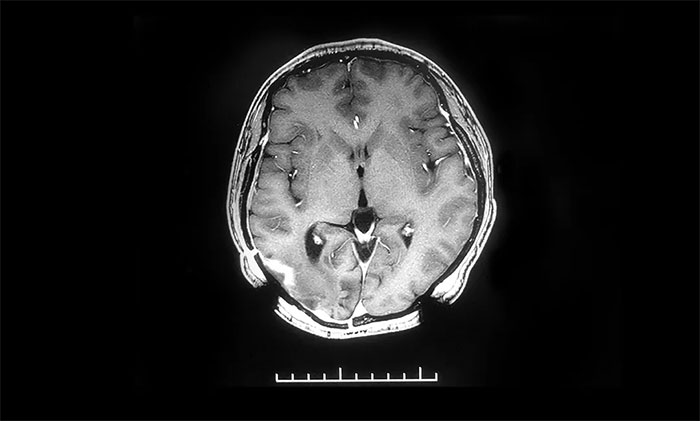

▲治疗后

近期,患者来医院复查,头颅MR提示原右侧颞枕叶胶质瘤术后改变,较前片病灶明显缩小。后续还将根据患者病情变化,有针对性地调整治疗,力求延长患者生存期,提高生存质量。